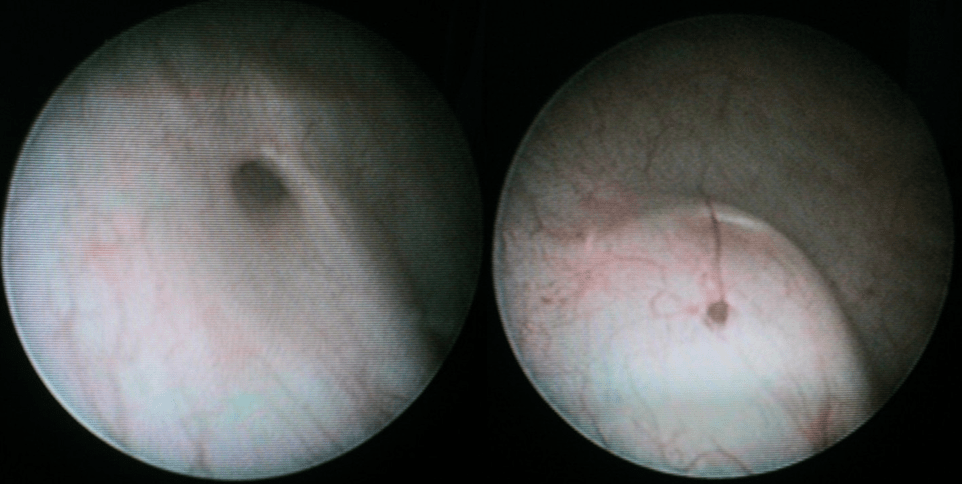

Il RVU è un fenomeno dinamico ed intermittente di risalita retrograda di urina (reflusso), di grado variabile, dalla vescica alla via urinaria superiore. Esiste una profonda differenza tra la condizione “primitiva”, geneticamente determinata e frequentemente associata ad un danno renale che nasce con il bambino (displasia renale) rispetto ad una condizione “secondaria” legata ad una alterazione funzionale vescicale o neurologica che può portare ad un danno pielo-nefritico acquisito (cicatrice renale–scar) ed irreversibile.

Proteggere i reni e prevenire la progressione di un potenziale danno renale è uno degli obiettivi primari dell’Urologo Pediatra Suo compito precipuo è quello di identificare correttamente il tipo di RVU e di sapere quale modalità terapeutica applicare, in considerazione di tutte quelle molteplici variabili che sono presenti (età, sesso,grado,etc.).